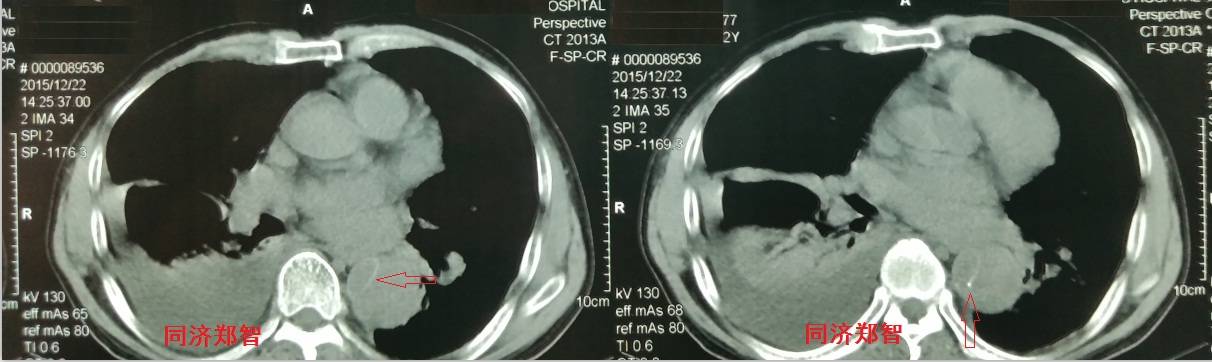

病例四

腹部平扫CT提示腹主动脉增宽,CTA证实为腹主动脉局限性夹层(红箭头所示)